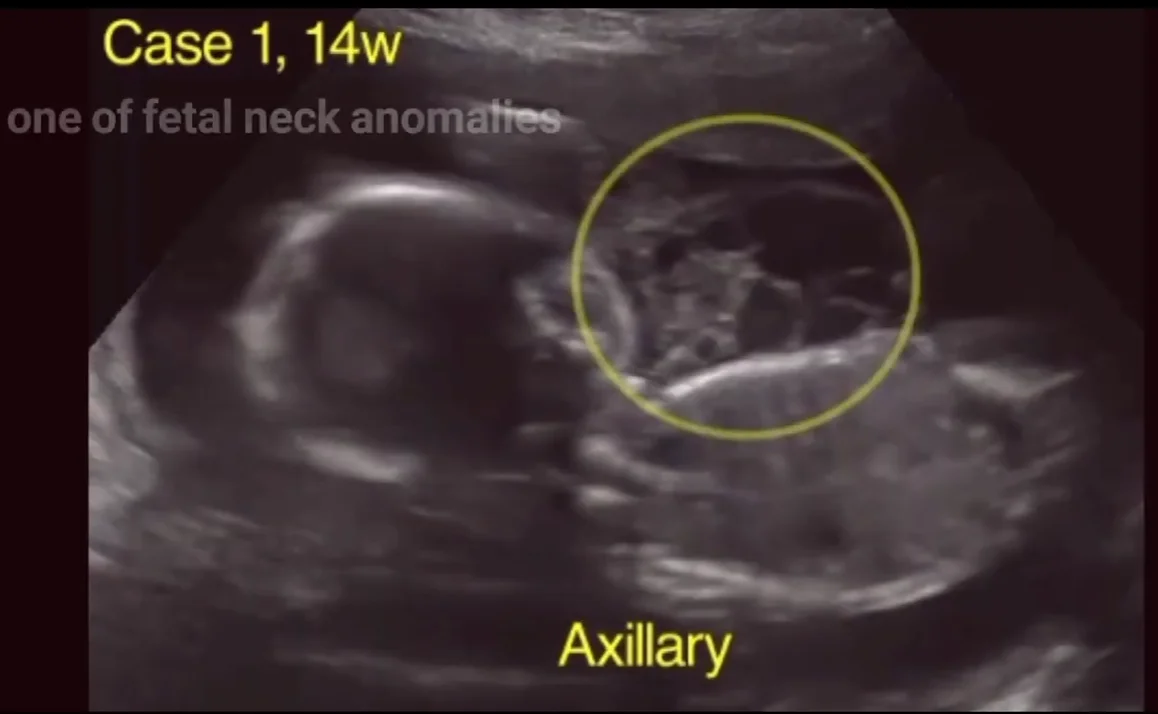

U, dị dạng bạch huyết vùng nách thai nhi (Lymphangioma)

01/04/2026